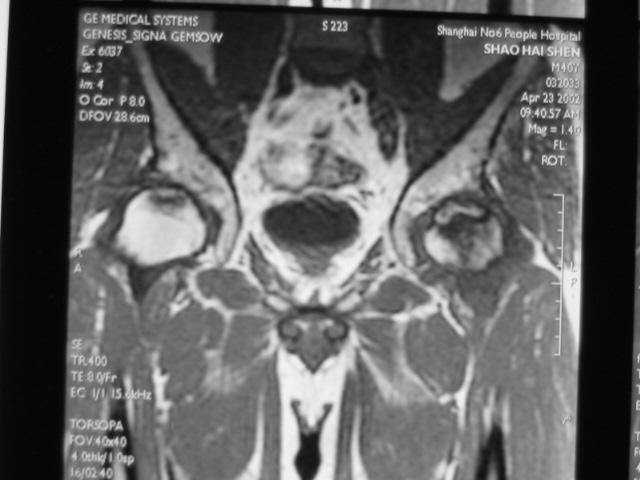

MRI诊断

Ⅲ期

髋关节间隙正常,无狭窄。

股骨头表面毛糙、开始变形。

软骨下皮质出现骨折,进一步发展出现轻微塌陷、阶梯状改变。

新月体形成:新月体代表无法修复的坏死骨发生引力性骨折,在T1W上为带状低信号区,T2W上,由于细胞内液渗出或关节液充填骨折线而呈高信号

股骨头表面软骨的完全性受到一定影响。